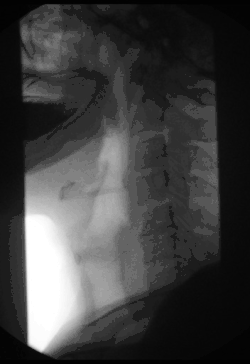

Fluoroscopy can be used to examine the digestive system using a substance that is opaque to X-rays (usually barium sulfate or gastrografin), which is introduced into the digestive system either by swallowing or as an enema. This is normally as part of a double-contrast technique, using positive and negative contrast. Barium sulfate coats the walls of the digestive tract (positive contrast), which allows the shape of the digestive tract to be outlined as white or clear on an X-ray. Air may then be introduced (negative contrast), which looks black on the film. The barium meal is an example of a contrast agent swallowed to examine the upper digestive tract. While soluble barium compounds are very toxic, the insoluble barium sulfate is nontoxic because its low solubility prevents the body from absorbing it. Investigations of the gastrointestinal tract include barium enemas, defecating proctograms, barium meals and swallows, and enteroclysis.[8]